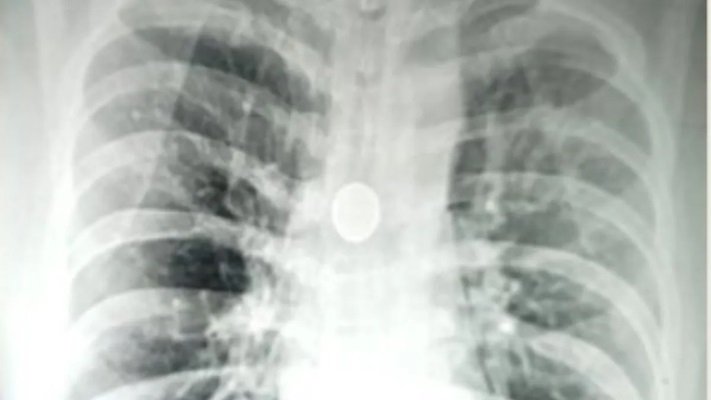

वाराणसी । अगर किसी शख्स की सांस नली में 25 पैसे का सिक्का पिछले 8 वर्षों से फंसा हो तो आप खुद समझ सकते हैं कि उसे किस तरह की परेशानियों से दो चार होना पड़ता होगा। लेकिन बनारस हिंदू विश्वविद्यालय (बीएचयू) के श्री सुंदरलाल अस्पताल के डॉक्टरों ने एक बेहद मुश्किल सर्जरी में एक 40 वर्षीय व्यक्ति की श्वास नली (श्वांस नली) में पिछले आठ वर्षों से फंसा 25 पैसे का सिक्का निकाला है। कार्डियो-थोरेसिक सर्जन प्रोफेसर सिद्धार्थ लखोटिया और प्रोफेसर एसके माथुर के नेतृत्व में डॉक्टरों की एक टीम ने मंगलवार को 20 मिनट तक चले ऑपरेशन में श्वास नली से सिक्का निकाला।

मरीज की सांस की नली से सिक्का निकालने में अहम भूमिका निभाने वाली एनेस्थिसियोलॉजी विभाग की डॉ. अमृता रथ ने कहा, “इस तरह के ऑपरेशन के लिए हाई लेवल की सटीकता की आवश्यकता होती है और थोड़ी सी भी गलती जीवन के लिए खतरा बन सकती है। सिक्के को निकालने के लिए एक एडवांस्ड रिजिड ब्रोंकोस्कोप का इस्तेमाल किया गया।(वीएनएस)